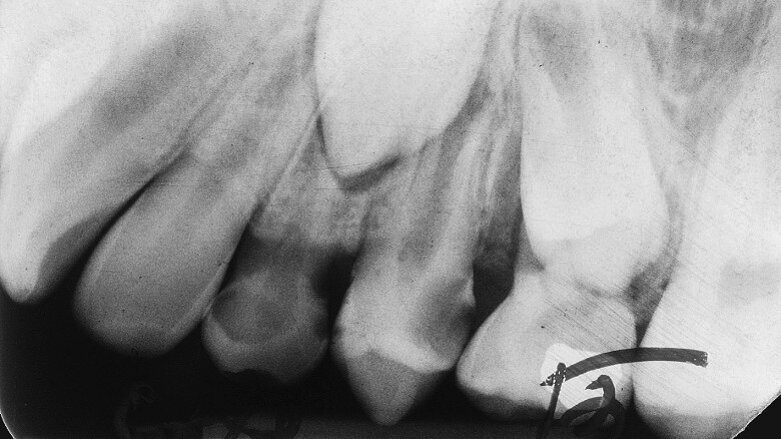

Fig. 3a: 18 March 1997 ante pulpotomy.

Case 1: Male (born 5 June 1987): Tooth 35

Fig. 3b: 18 March 1997 post pulpotomy